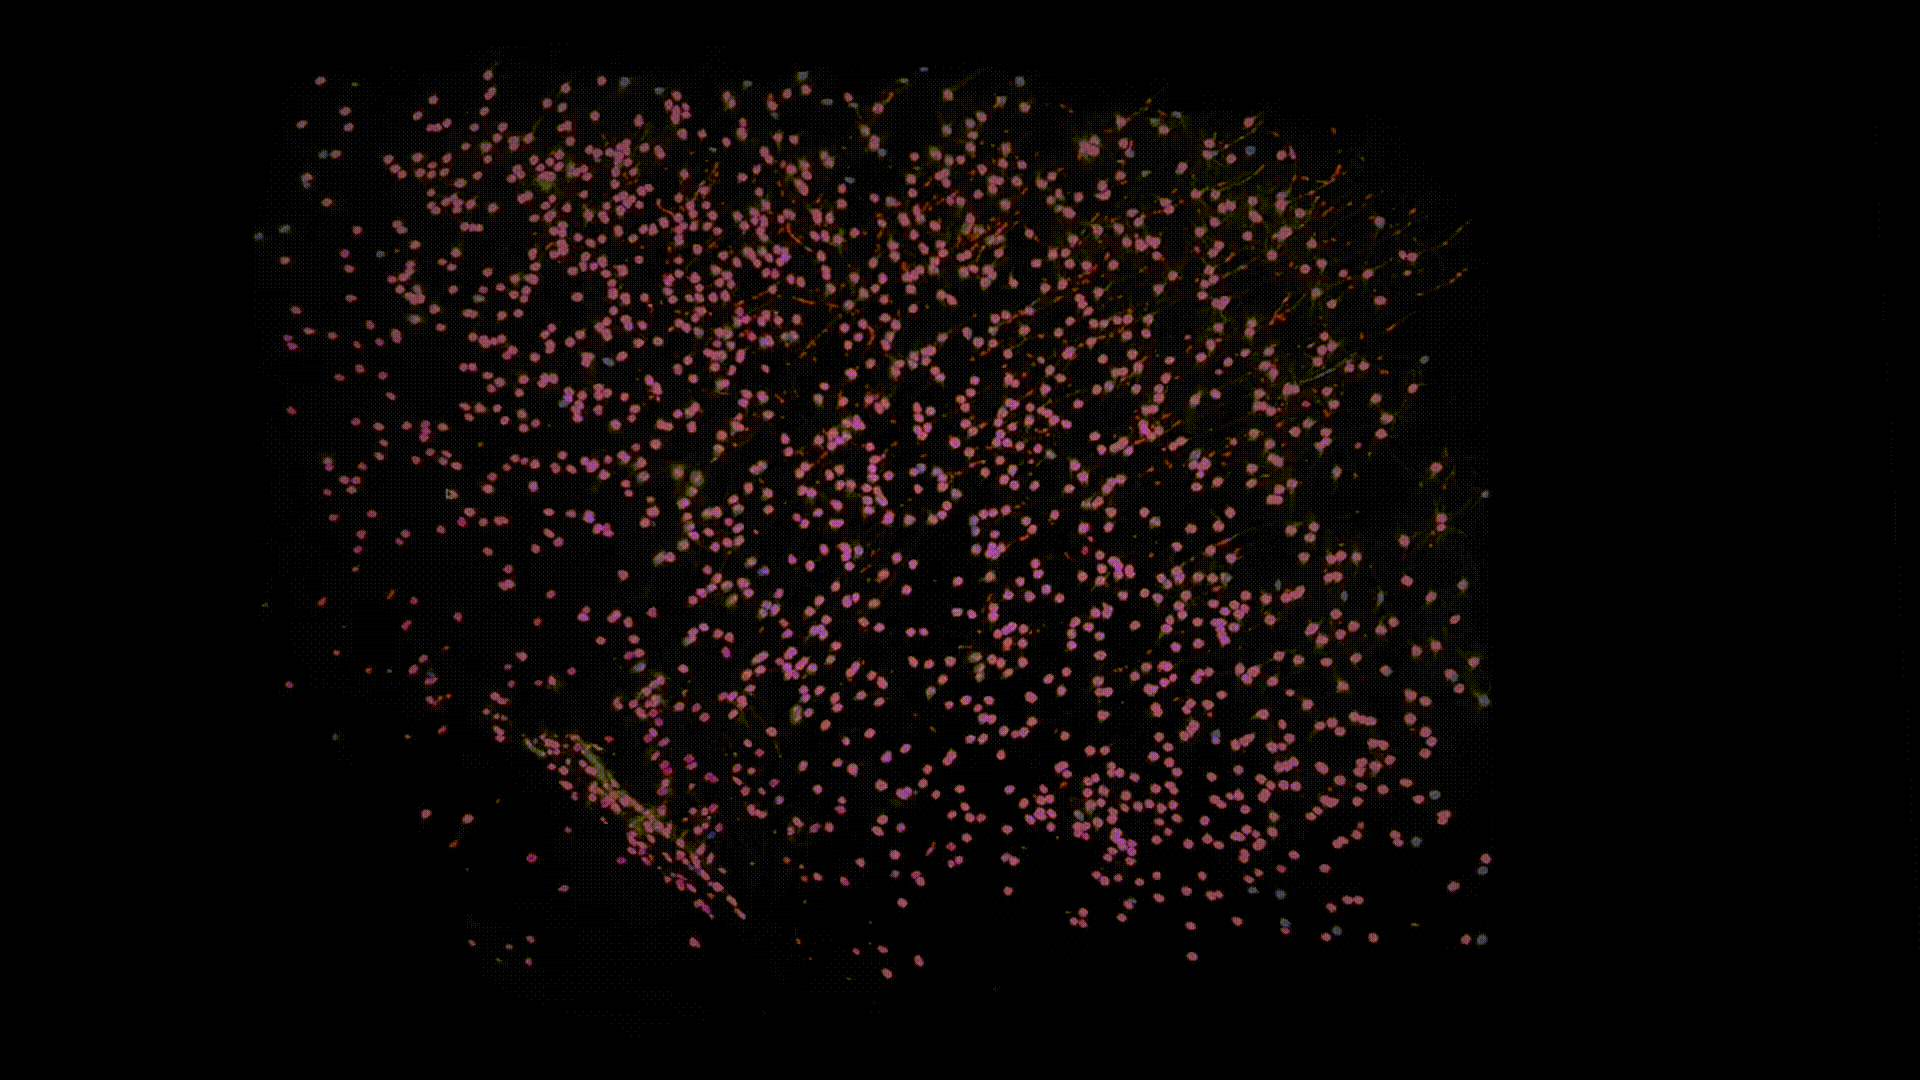

Thanks to recent advances in tissue clearing technology and light sheet fluorescence microscopy (LSFM) imaging techniques, we can obtain a transparent whole brain image of neuronal cell bodies in mice. Below is an example of the data that I have worked with.